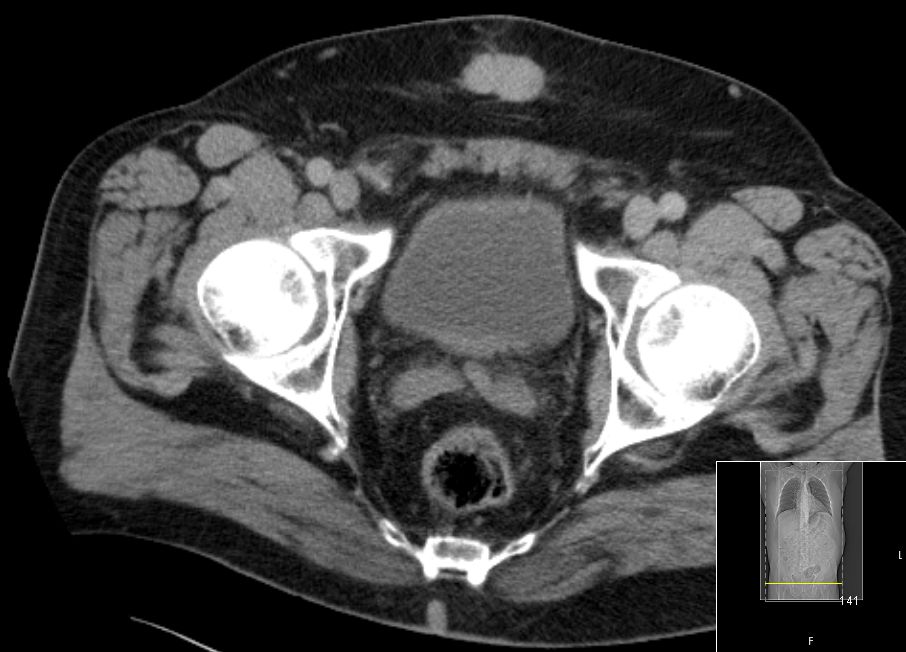

| Lymphknoten | 73-jähriger Mann, der vor 2 Jahren ein Sigmakarzinom Stadium IIIB hatte.

Jetzt Anastomosenrezidiv, Leber- und Lungenmetastasen.

Hier: zahlreiche vergrößerte Lymphknoten paraaortal, paracaval und mesenterial.![]() | ||